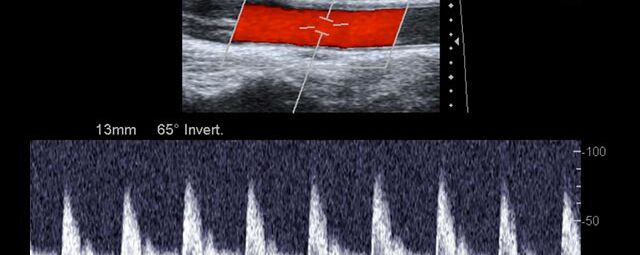

Die Sonographie ist ein bildgebendes Verfahren in der medizinischen Diagnostik, das mit Ultraschallwellen arbeitet. Ultraschall ist Schall mit einer Frequenz oberhalb der menschlichen Hörgrenze. Im medizinischen Bereich werden je nach Körperregion Ultraschallwellen in einem Frequenzbereich von ca. 3,5 – 18 Mhz verwendet. Die körpernahe Ultraschallsonde sendet durch einen piezoelektrischen Effekt kurze Schallwellenimpulse in den Körper. Ultraschall-Gel stellt den Kontakt zwischen Sonde und Körper her. Je nach Gewebeart werden diese Schallwellen im Körper unterschiedlich stark reflektiert. Anhand des zurückgesendeten Schallmusters kann das Ultraschallgerät Schnittbilder berechnen, auf denen die Organe des Körpers nach krankhaften Veränderungen untersucht werden können.

Der Arzt bewegt den Schallkopf mit leichtem Druck in verschiedene Richtungen. Die zu untersuchenden Strukturen können somit aus verschiedenen Perspektiven betrachtet werden. Aussagekräftige Bilder werden festgehalten und digital archiviert, Strukturen oder Organe können zusätzlich vermessen werden. Ein kurzes Befundgespräch erfolgt direkt nach der Untersuchung. Ihr zuweisender Arzt erhält von uns schriftlich einen ausführlichen Befundbericht.